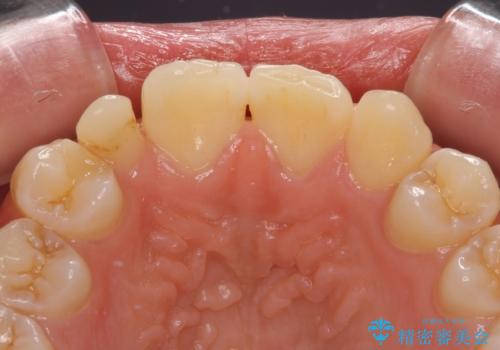

- 他院で矯正治療を終え、上顎前から2番目の歯の大きさを気にして来院された患者様です。

右側は小さく、左側は欠損により犬歯が前から2番に来ている状態でした。

矯正治療の段階で、矮小歯は前後にスペースが作ってあったため、極力左右対称の歯冠形態となるように補綴治療を行うこととしました。

歯根の太さや幅が左右で異なるため、歯肉ラインはどうしても左右非対称となってしまいますが、とても自然な口元となりました。